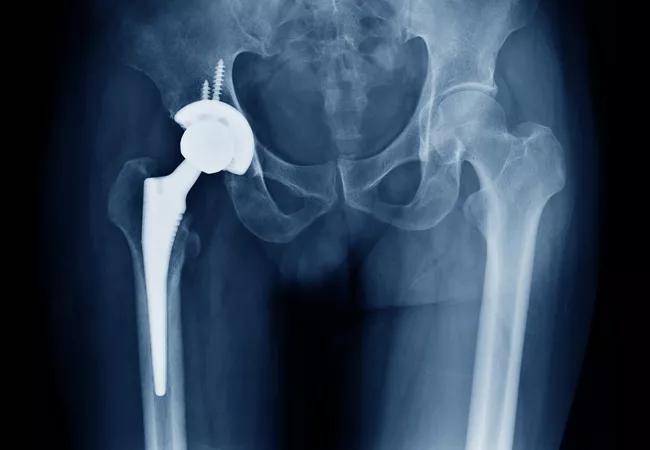

A Potential Treatment for Periprosthetic Joint Infection after Total Joint Arthroplasty

Infection after total joint arthroplasty is a devastating complication made exceptionally problematic due to the difficulties in diagnosing and treating such infections. The current options to treat chronic infections, including one-stage or two-stage revision surgeries, do not always eradicate these infections and are relatively high in morbidity.

There is a need for innovative methods for biofilm disruption and infection eradication, which may optimize the effects of antibiotics or even potentially offer an alternative to antibiotic strategies. If the biofilm and bacteria can be suppressed or eradicated without the use of extensive surgery and potentially preserve the prosthesis, then the devastating effects of periprosthetic joint infection (PJI) can be mitigated.